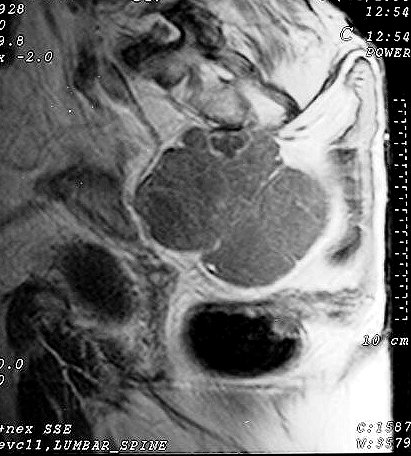

Сакральная хордома. Д-р Марсело Сенна Ксавье де Лима, Paul Roland Kaleff, и Антонио Рожерио del'Arco Roth Аугусто Варгас. Рецидив. Часть крестца была удалена ранее. Пнд, 27/11/2017 - 21:03 #1 Катенёв Валенти... Не на сайте Был на сайте: 7 лет 4 месяцев назад Зарегистрирован: 22.03.2008 - 22:15 Публикации: 54876 Внутричерепная хордома. http://pubs.rsna.org/doi/full/10.1148/rg.234025176 Пнд, 09/07/2018 - 20:44 #2 Катенёв Валенти... Не на сайте Был на сайте: 7 лет 4 месяцев назад Зарегистрирован: 22.03.2008 - 22:15 Публикации: 54876 Продолжение. Приложения: